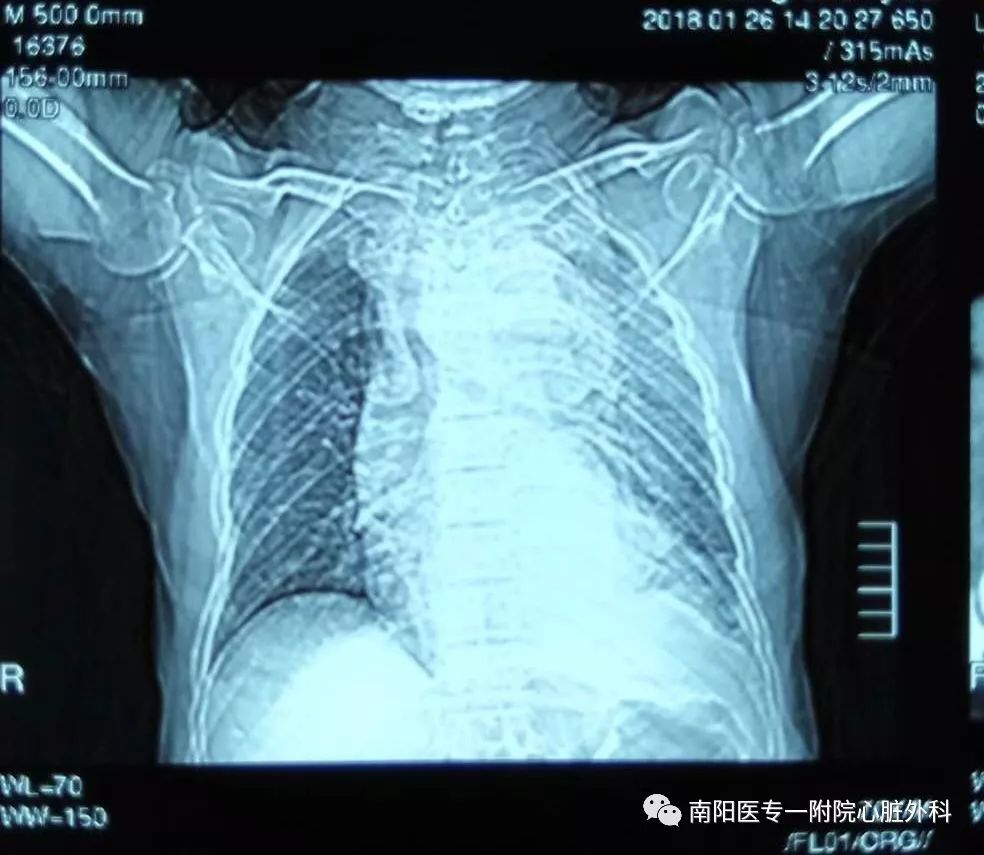

几天前我市迎来今冬第二场大雪,家住卧龙区某镇70高龄的王老伯在家铲雪,突然出现胸背部疼痛,逐渐出现腰疼,自认为扭腰了,在家休息到第二天仍感疼痛,就到镇卫生院就诊,怀疑腰扭伤,行腰椎CT检查提示腰椎间盘膨出,给予活血化瘀药物,王老伯仍觉症状不见减轻,又拍胸片提示气管右移,纵膈稍增宽待查,再行胸部CT进一步检查,提示纵膈占位、左侧肺不张、胸腔积液、支气管炎,怀疑是肿瘤肿块,晚上出现声音嘶哑的表现。

第三天来到我院胸外科住院,我科会诊时发现:患者突发胸背部疼痛,纵膈增宽,气管向右侧移位,声音嘶哑,胸腔积液,CT片上隐约可见降主动脉出现真假腔,高度怀疑主动脉夹层。